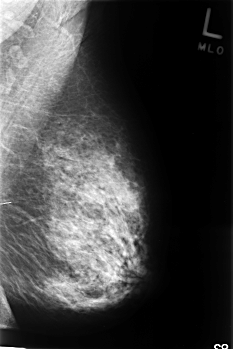

C_0350_1.LEFT_MLO

LEFT_MLO LINES 4536 PIXELS_PER_LINE 3024 BITS_PER_PIXEL 12 RESOLUTION 50 NON_OVERLAY